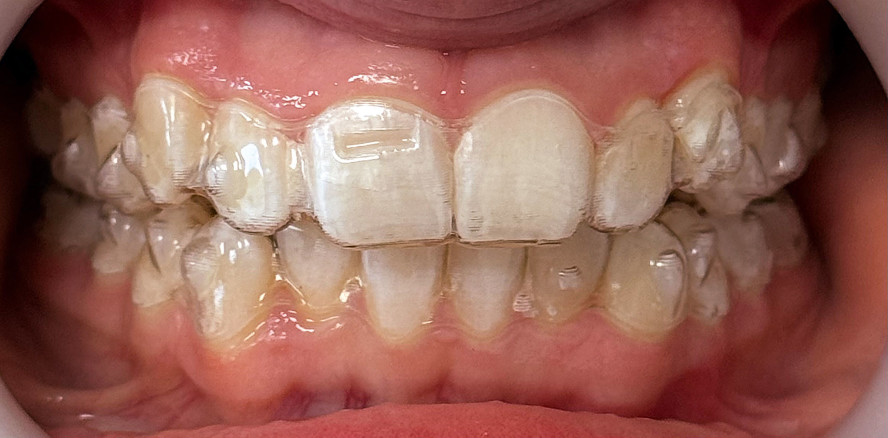

Aufbissschienen sind in der Zahnmedizin ein bewährtes Instrument mit einem breiten Anwendungsspektrum – von der Funktionsdiagnostik über die Behandlung...

Aufbissschienen sind in der Zahnmedizin ein bewährtes Instrument mit einem breiten Anwendungsspektrum...